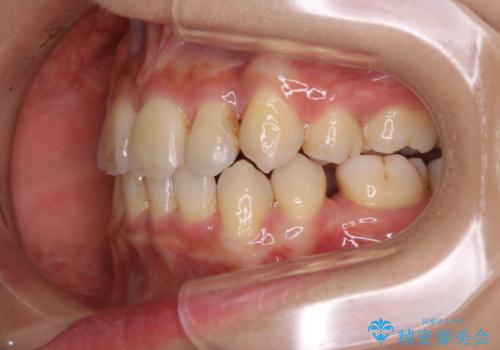

PMTC60分コースを行いました。紅茶による着色が全体的に付着していました。

インビザライン中の患者様で、紅茶を飲んだ後にそのままマウスピースをはめていたそうです。着色が、かなり目立っていた為、追加アライナーのタイミングで全体の着色を除去し、とても綺麗になりました。